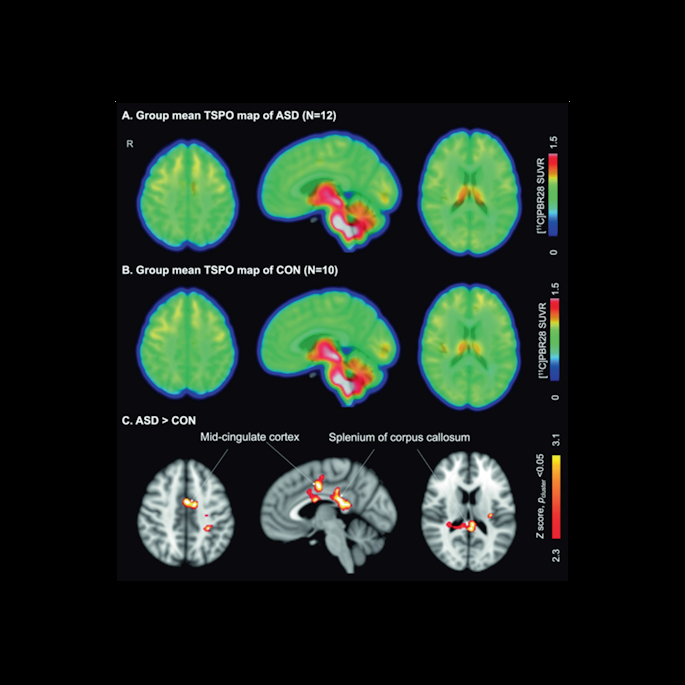

A visual abstract of the study. Image courtesy of the Journal of Nuclear Medicine.